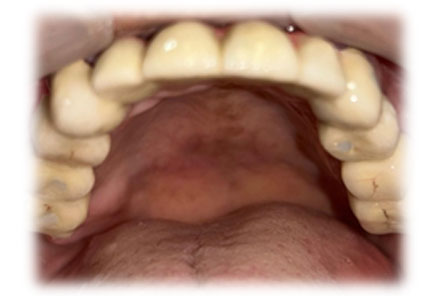

Guided Implant Surgery involves the use of advanced 3D imaging and computer-aided design (CAD) to plan the exact placement of dental implants. This meticulous planning process allows our dental specialists to visualize the patient’s oral anatomy in great detail, ensuring the implants are placed in the most ideal position for both functionality and aesthetics. The procedure is tailored to each patient's unique needs, ensuring a personalized treatment plan.

Whether you need a single tooth replacement or a full arch restoration, our Guided Implant Surgery service ensures that you receive the best possible care with minimal discomfort. Trust Pushti Dental Clinic and Pediatric Dental Center for advanced dental solutions that restore your smile and confidence.